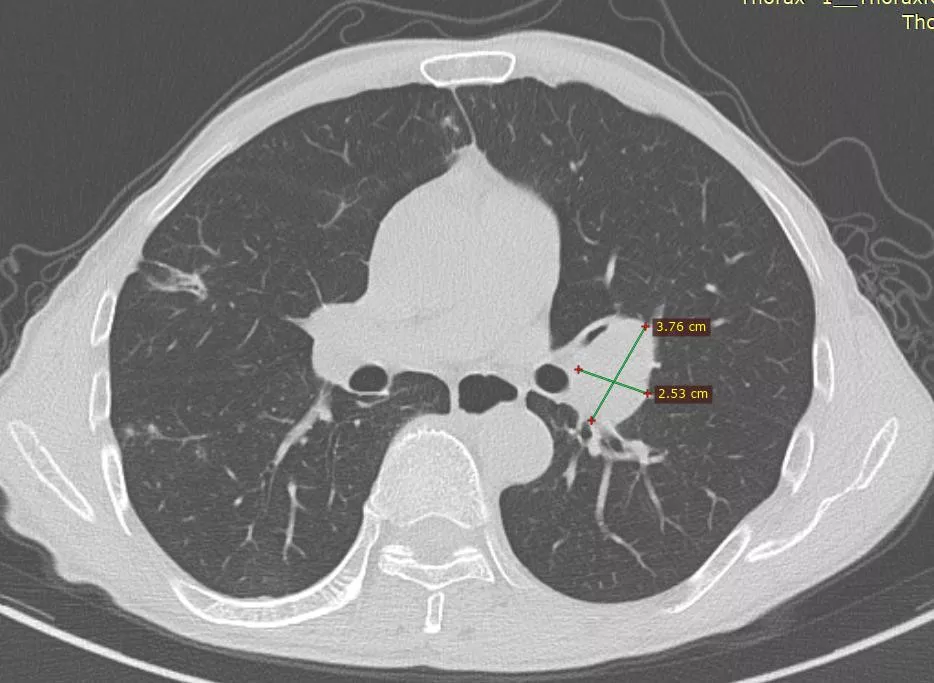

快速缩瘤持续获益免疫治疗为晚期食管鳞癌患者开启新的治疗时代

图片尺寸1080x709